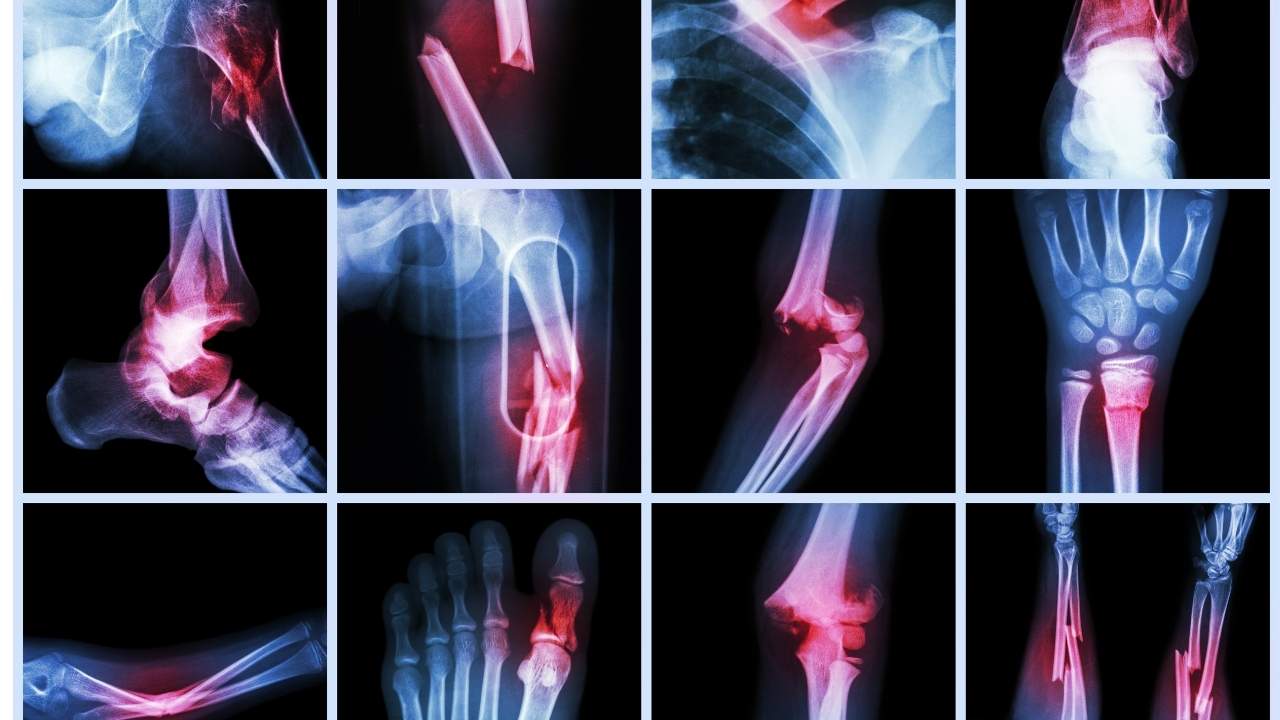

شکستگی استخوان یکی از شایعترین آسیبها در دنیای پزشکی است که ممکن است هر فردی در هر سنی با آن مواجه شود. انواع شکستگی استخوان میتواند ناشی از حوادث ناگهانی مانند سقوط، تصادف یا ضربههای مستقیم به استخوان باشد.

بهطور کلی، شکستگیها به دو دسته عمده تقسیم میشوند؛ «شکستگیهای بسته» که در آن پوست سالم باقی میماند و «شکستگیهای باز» که در این حالت، استخوان از پوست خارج میشود.

انواع شکستگی استخوان

شامل موارد زیر است:

- شکستگی باز (Open Fracture): در این نوع شکستگی، استخوان از پوست خارج میشود و خطر عفونت بهشدت افزایش مییابد.

- شکستگی بسته (Closed Fracture): استخوان در زیر پوست شکسته میشود، اما پوست سالم باقی میماند. در این عارضه معمولاً خطر عفونت کمتر است.

- شکستگی کامل (Complete Fracture): استخوان بهطور کامل شکسته شده و دو تکه مجزا ایجاد میکند.

- شکستگی ناقص (Incomplete Fracture): استخوان بهطور جزئی شکسته میشود و ممکن است شکستگی بهصورت ترک باشد.

- شکستگی ساده (Simple Fracture): در این حالت، استخوان بهطور مستقیم شکسته شده و بدون آسیب به بافتهای اطراف است.

- شکستگی پیچیده (Complicated Fracture): این نوع شکستگی به عروق، اعصاب یا بافتهای نرم آسیب میزند و نیاز به درمان فوری دارد.

- تصویربرداری با اشعه ایکس: این روش مرسومترین و ابتداییترین روش برای تشخیص شکستگی ااست. اشعه ایکس تصویر واضحی از استخوانهای آسیبدیده ارائه میدهد و نوع و شدت شکستگی را مشخص میکند.